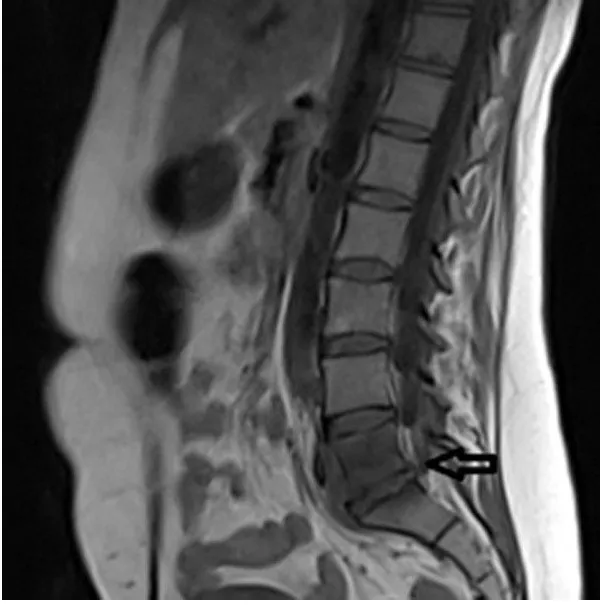

El reumatismo palindrómico es una enfermedad de causa desconocida, caracterizada por ataques recurrentes y frecuentes de inflamación articular aguda que ocurren a intervalos irregulares. Estos episodios se manifiestan con dolor…